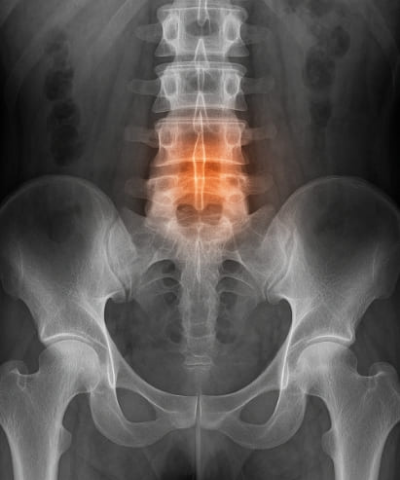

척추관 협착증은 척추의 신경이 지나가는 통로인 척추관(spinal canal) 이 좁아지면서, 신경을 압박해 통증과 이상 감각을 유발하는 질환입니다. 50대 이상 중장년층에서 자주 발생하며, 허리, 엉덩이, 다리의 저림과 통증, 오래 서있기 힘든 증상이 특징입니다.

척추관 협착증의 원인과 증상 정리

척추관 협착증 원인

- 척추 디스크의 퇴행성 변화

- 인대의 비후

- 후관절 관절염

- 요추 전방전위증

- 외상, 선천적 척추관 협소

대표 증상

- 서있을 때 통증이 심하고 앉거나 앞으로 구부리면 완화됨

- 허리, 엉덩이, 다리까지 이어지는 저림 또는 통증

- 보행 시 점차 다리에 힘이 빠짐

- 다리 감각 저하, 간헐적 파행